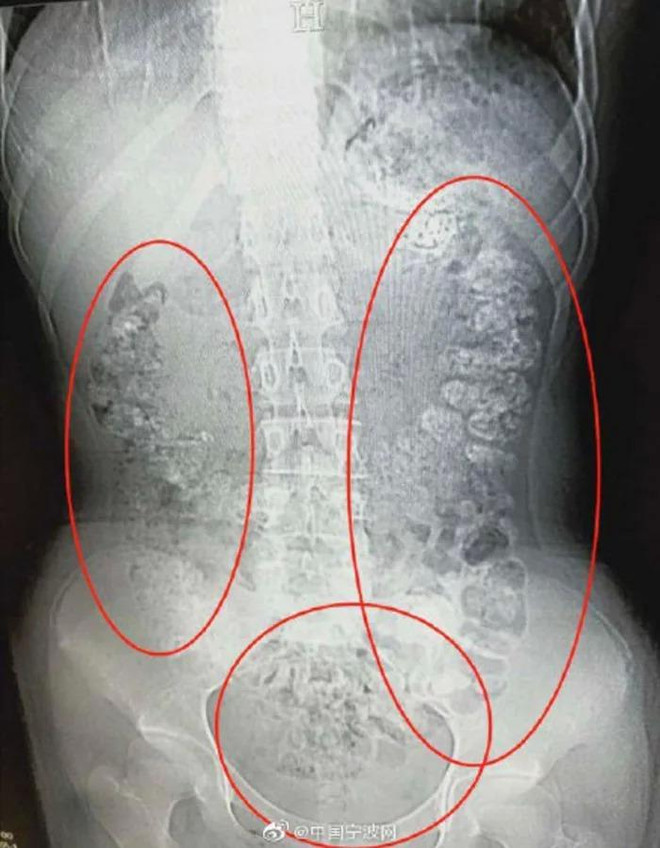

Phát hiện hàng trăm hạt trân châu chưa tiêu hóa trong bụng một cô bé ảnh 1Các hạt trân châu chưa được tiêu hóa hết. (Ảnh: 9GAG)

Phát hiện bụng cô bé phình to bất thường, các bác sỹ đã quyết định đưa bệnh nhân này đi chụp cắt lớp. Kết quả chụp cắt lớp cho thấy hàng trăm vật thể nhỏ hình tròn nằm trong khắp các cơ quan nội tạng, từ dạ dày, đại tràng, ruột và hậu môn.

Sau khi cùng nhau thảo luận, các bác sỹ kết luận những vật thể nhỏ này là các hạt trân châu chưa được tiêu hóa hết. Bác sỹ Zhang Louwei đã hỏi cô bé xem bệnh nhân có ăn gì khó tiêu trong vài ngày qua hay không. Cô bé thừa nhận đã uống một cốc trà sữa từ 5 ngày trước khi nhập viện.

Phát hiện hàng trăm hạt trân châu chưa tiêu hóa trong bụng một cô bé ảnh 2Các hạt trân châu vẫn mắc kẹt trong hệ tiêu hóa. (Ảnh: 9GAG)